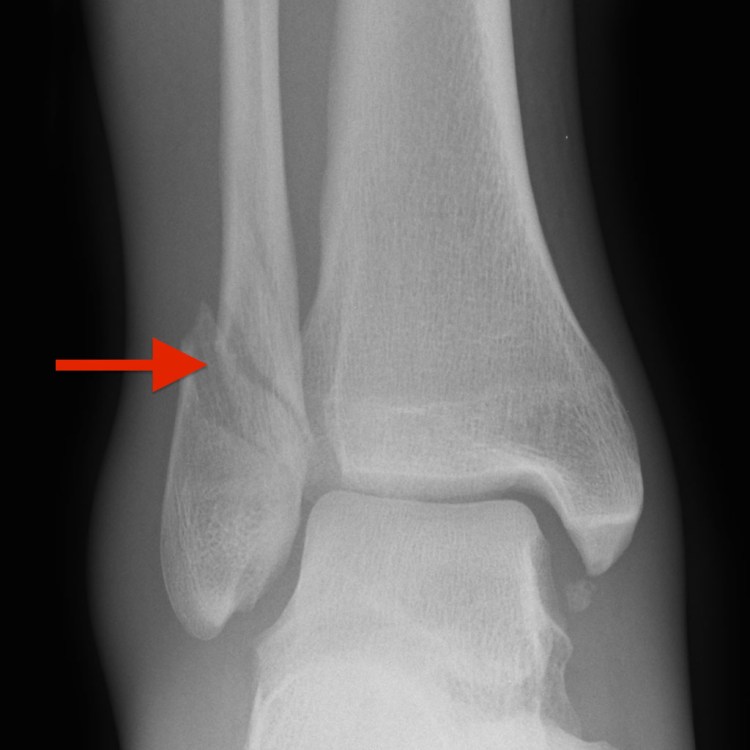

Covering all the common injuries and pain our feet and ankles experience over a lifetime. Click on the links below for more information.